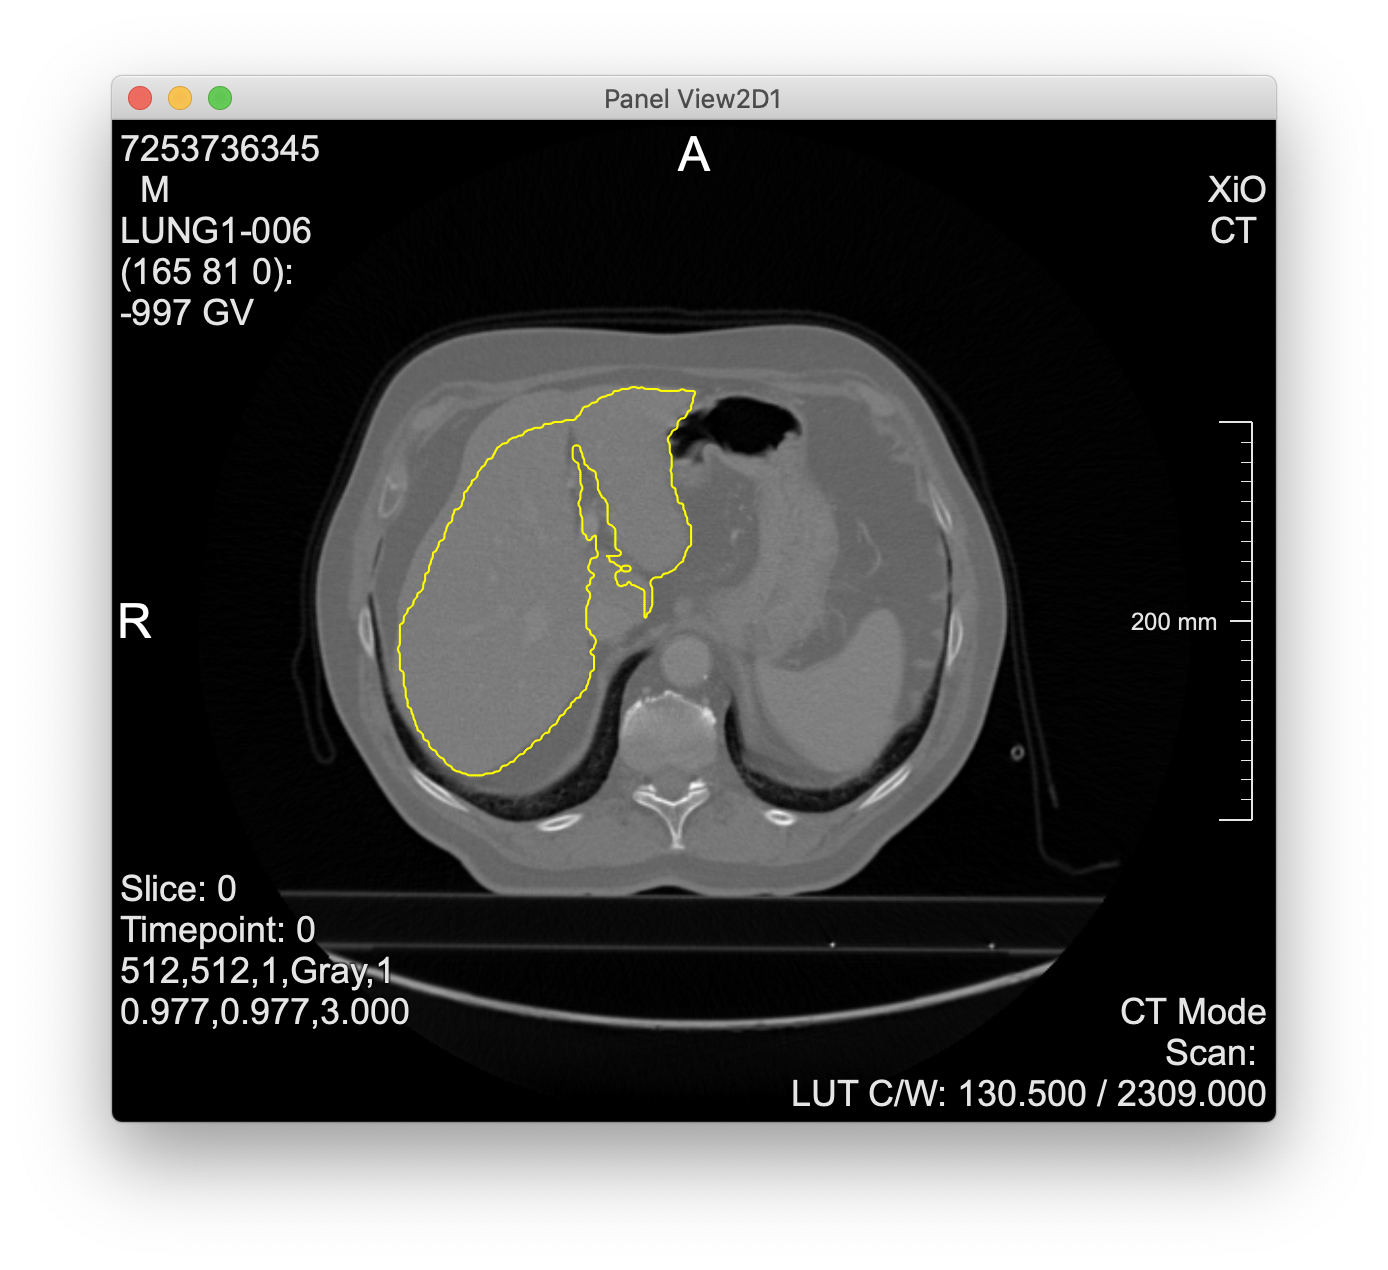

- Evaluation of cascaded-fcn-liver

- takes a single CT slice as DICOM file via a form-encoded POST request

- returns contours as voxel coordinates in JSON format

- screenshot from MeVisLab experiments below

- “cascaded” = two networks for liver + tumor segmentation, but the API runs only the first (the second is included, but execution is left to the user)

Liver contours computed via the cascaded-fcn-liver model parsed and visualized in MeVisLab: